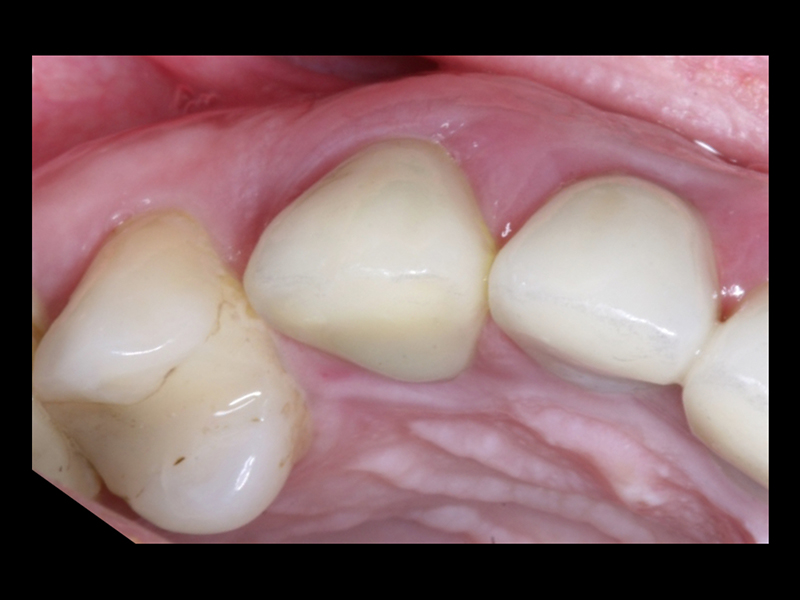

- Conforto e Estética: A prótese provisória é funcional e visualmente semelhante aos dentes naturais.